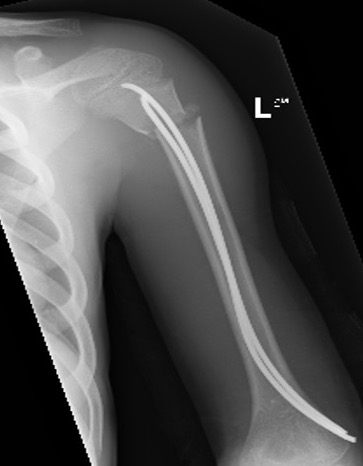

Case: 18 year old boy

Initial xray 18 month xray

Retrograde flexible nails

Surgical technique TENS proximal humerus PDF

Youtube surgical technique TENS proximal humerus video

Technique

2 x drill holes in lateral supracondylar ridge

- 1 cm proximal to lateral epicondyle

- pass 2 x TENS

- standard 0.4 of diameter of bone

- usually 2.5 mm

Results

Marengo et al. J Paediatr Orthop 2015

- 14 patients average age 10 years treated with retrograde flexible nails

- no loss of position, no growth arrest